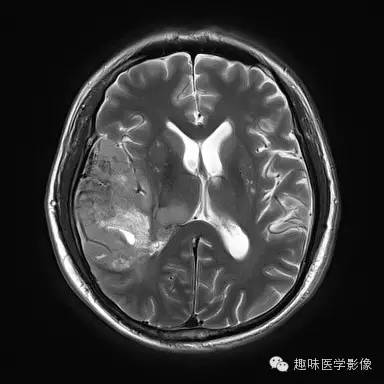

性别:男年龄:48岁 间断性四肢抽搐9月余,头晕伴肢体无力1月余

右侧颞顶叶、丘脑可见大片不规则异常信号灶,局部脑回肿胀,大小约45×75mm,T1WI呈混杂低信号,内可见多发条状高信号,中央可见更低信号灶,T2WI/FLAIR呈混杂稍高信号,内可见点状低信号,DWI呈混杂高信号,未见明显占位效应,增强后呈多发不规则花环状明显强化灶,内可见多发点状小血管影。

少突胶质细胞瘤,WHOⅡ级。

少突胶质细胞瘤为分化良好、生长缓慢但呈浸润性的肿瘤,典型者累及皮层和皮层下白质,20%-50%有侵袭性(间变性少突胶质瘤)。最佳诊断征象:部分钙化 中年人的皮层肿块,可以侵蚀并使颅骨膨胀。CT平扫为低/等密度,大部分钙化,可有出血和囊变,增强CT表现多样,从无增强到明显增强。MRI常不均匀,T1WI上相对于皮层为低/等信号,T2WI为高信号;除间变外,出血、坏死少见,边界清楚,伴轻微水肿,50%强化。